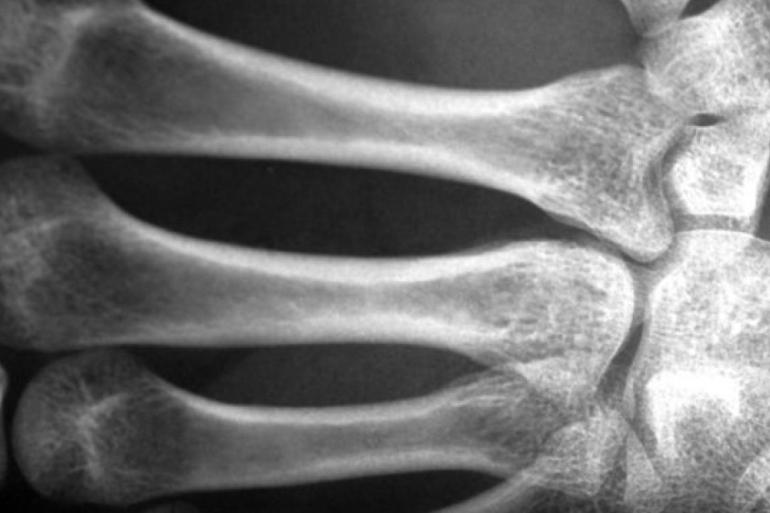

عمون - هشاشة العظام عبارة عن مرض يؤدي إلى ضعف ‫العظام، وهو ما يقود لسهولة انكسارها مع أي مجهود بسيط أو حركة خاطئة، وترتبط أكثر بالتقدم في العمر.

‫‫‫وبالنسبة للعديد من الحالات، تظل هشاشة العظام دون أن يلاحظها أحد لفترة ‫طويلة، ويمكن تسجيل علامات باستخدام قياسات واختبارات مختلفة، لكن يبقى ‫قياس كثافة العظام هو الفيصل، ‫وفي الماضي كان ينظر لهشاشة العظام على أنها عرض من أعراض الشيخوخة.

‫‫وفي المرحلة المتقدمة من المرض تقل حركة الأشخاص المصابين بشكل كبير، ‫ويمكن أن تحدث الكسور حتى مع الأحمال المنخفضة.